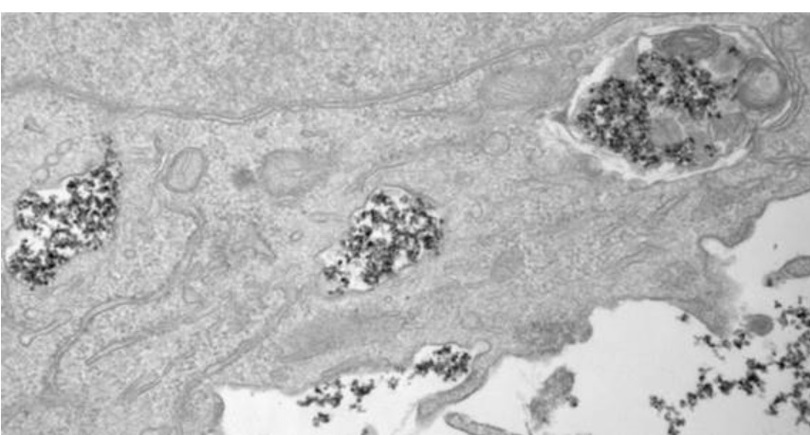

Nanopartículas magnéticas de metal, armas en la lucha contra el cáncer

Las nanopartículas de óxido de hierro se emplean para liberar fármacos de forma localizada en el organismo, eliminar células tumorales mediante la emisión de calor (hipertermia) o realizar diagnósticos en resonancias magnéticas.